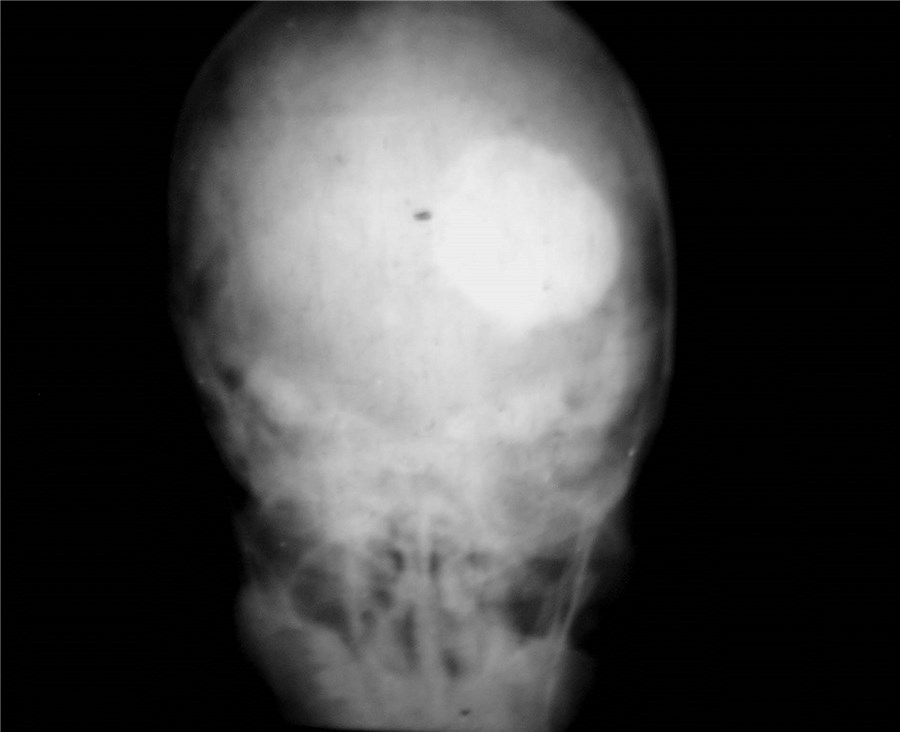

Craniopharyngioma

Craniopharyngioma is a common tumor in childhood, but can also be seen in adults. These tumors often present with endocrine problems, abnormalities of appetite, visual problems. MRI gives diagnosis and treatment involves surgery. Attempt must be made at complete excision, with safeguarding of vital hypothalamic functions. Radiation may be required after surgery to halt tumor followed by surgical excision, with excellent results.

Encephaloceles

Encephaloceles are often grotesque-looking congenital swellings arising from the head or face, that may make childbirth difficult. Child often appears to have a swelling as large as the head. Most of these swellings can be surgically removed successfully.